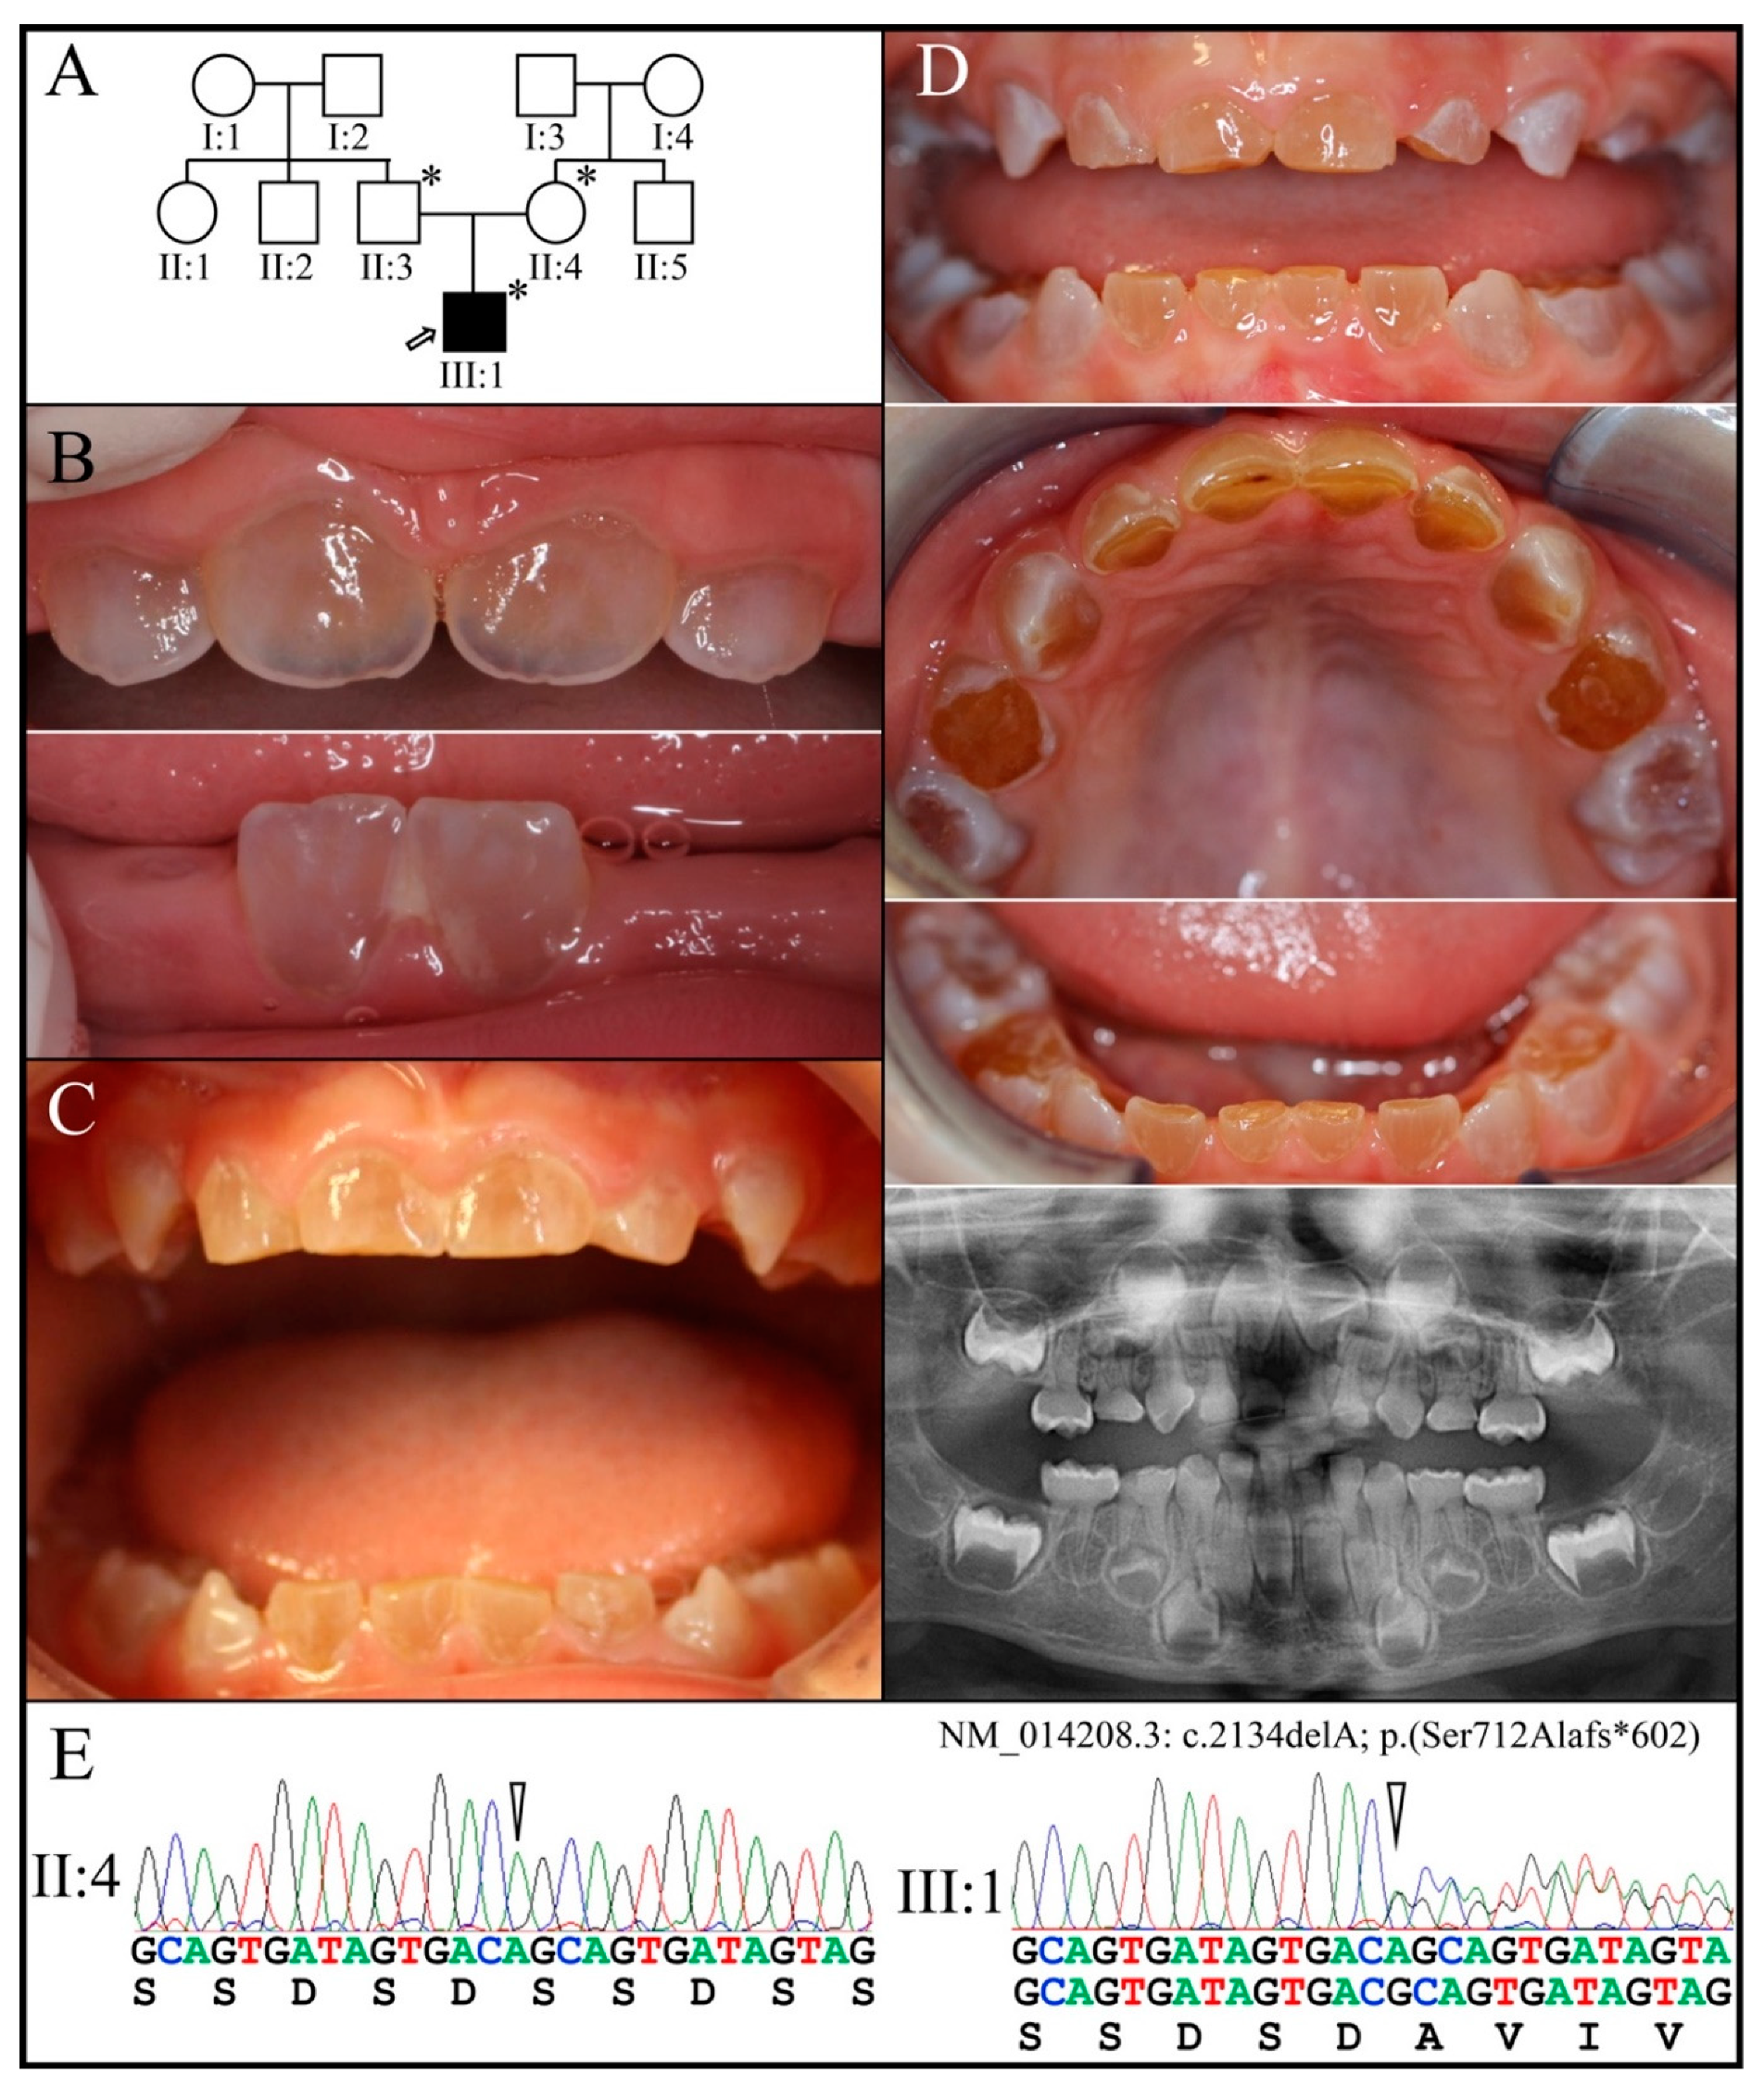

3.2. Four Families with DGI-III: 5′ DSPP Mutations

3.3. Eight Families with 3′ DSPP Mutations Causing DD-II or DGI-II